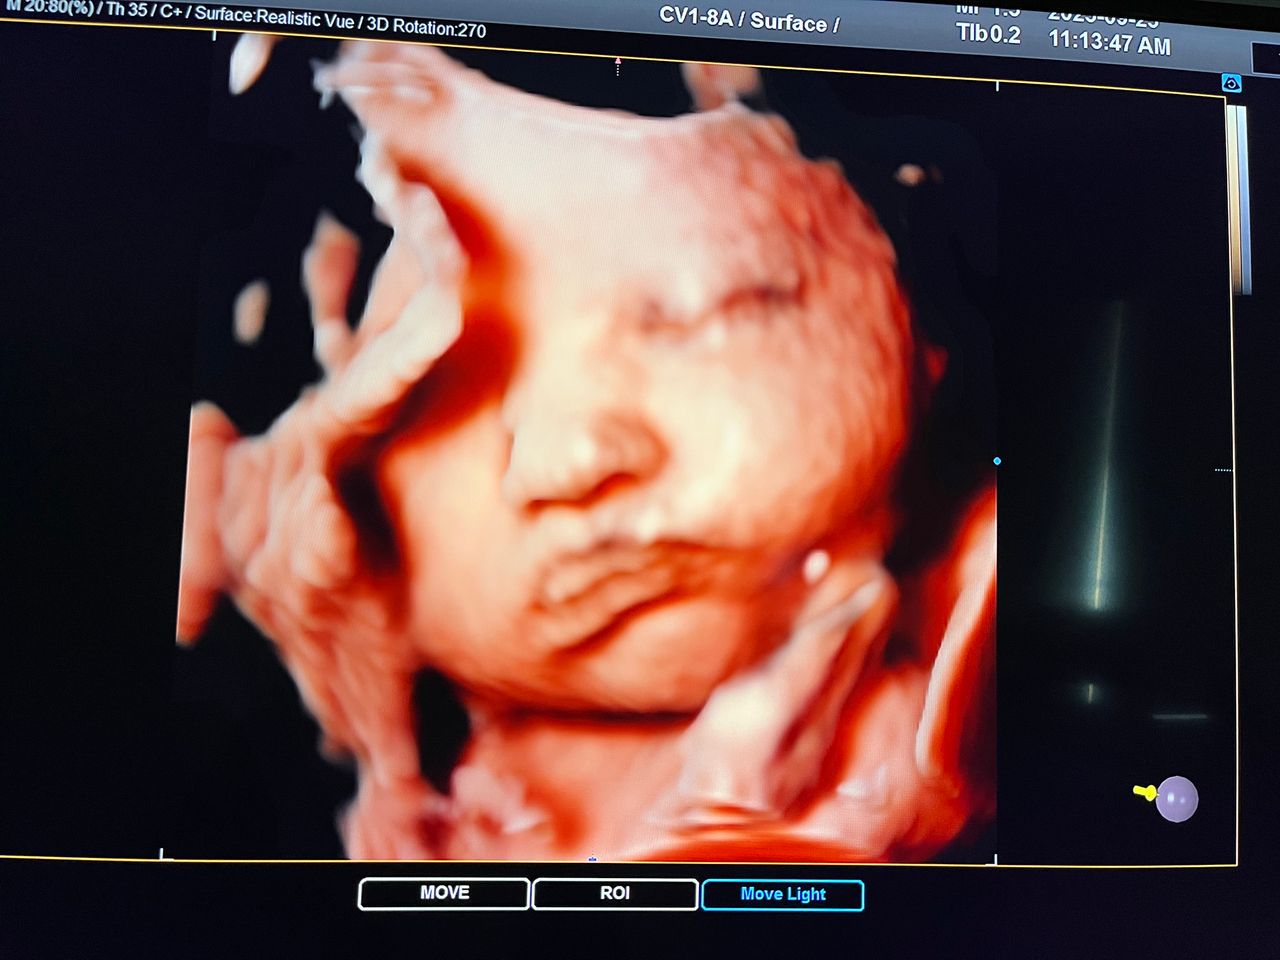

Attualmente lavoro come Dirigente medico nella SC di Ostetricia e Ginecologia dell'Ospedale Michele e Pietro Ferrero di Verduno, mi occupo prevalentemente di screening prenatale, ecografia ostetrica del I trimestre( misurazione translucenza nucale,NT), ecografia morfologica del II trimestre, ambulatorio pregresso taglio cesareo, ecografia ostetrica 3D. Seguo le gravidanze fisiologiche e quelle ad alto rischio , presto servizio in sala parto. Eseguo visite ginecologiche di I-II livello in regime ambulatoriale, counseling contraccettivo ed eventuale prescrizione pillola, inserimento spirale (IUD), dispositivo sottocutaneo (Nexplanon).

Foto e video